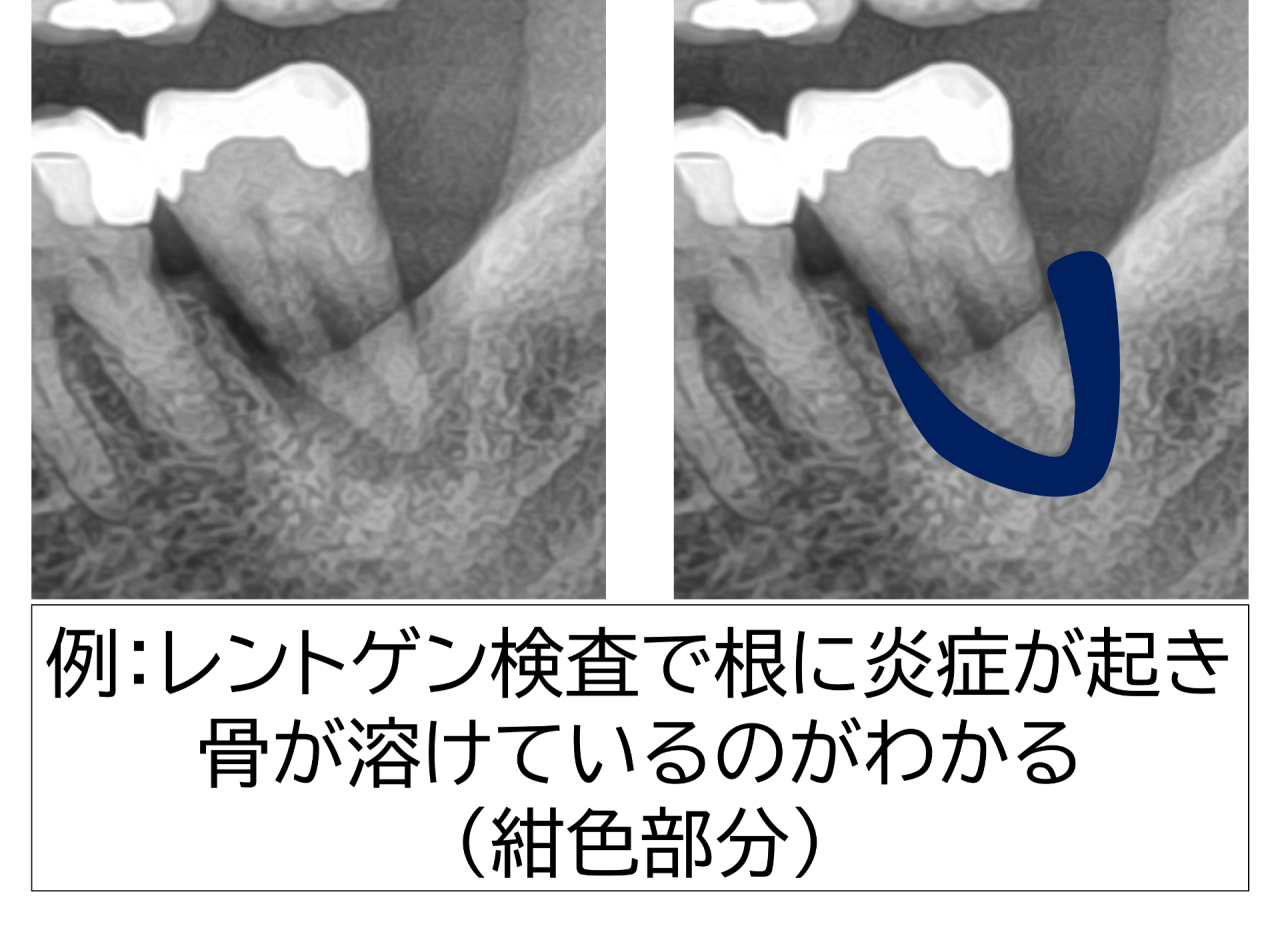

まずは、痛みや違和感が出ている歯の状態を確認します。 必要に応じてレントゲンを撮影し、根の中や周囲の骨の状態までしっかり調べます。 これにより、根の先で炎症が起きていないか、以前の治療の跡がどうなっているかも把握できます。